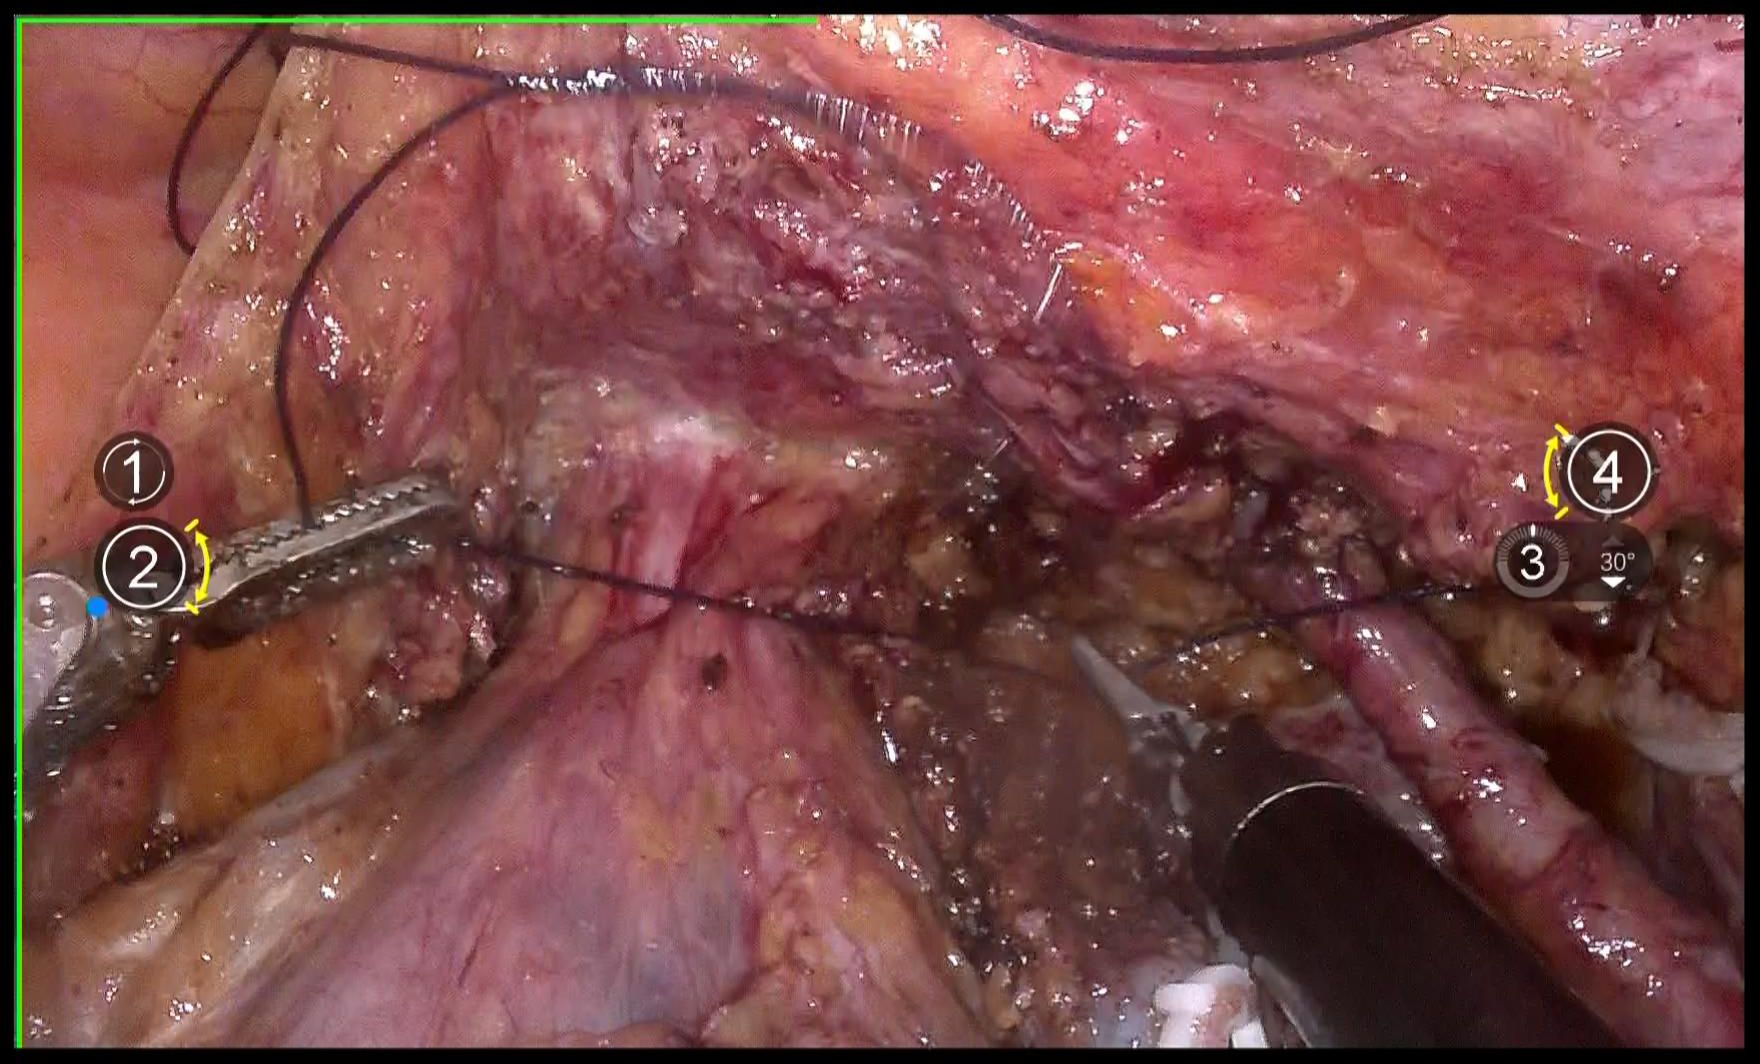

Use 1–0 barbed suture for continuous circular suturing of the vaginal wall to close the vagina. Ensure that during circular incision of the vagina, the cervical tumor does not spill out(Figure 7). It should be noted that the suture should be placed just caudal to the level of paracolpium transection. During suturing, the assistant must provide direct visual confirmation via the vaginal route, with particular attention to ensuring complete vaginal closure.

4.8 Flush and transect the vagina

Repeatedly irrigate the vagina with sterile distilled water at 42°C to dislodge any tumor cells adhering to the vaginal wall, thereby preventing the entry of tumor cells into the wound during circular incision of the vaginal wall(Figure 8). Then, transect the vagina with a monopolar and stump the vaginal with absorbable suturesl(Figures 9A, B).